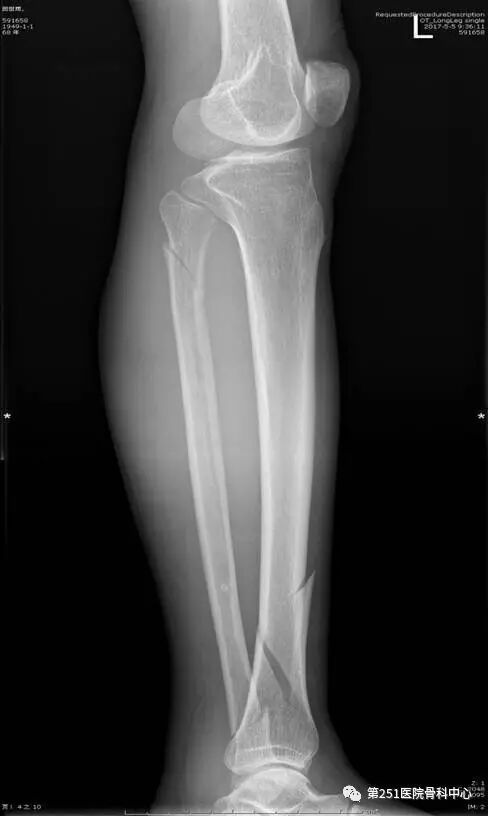

病例5:男性,64岁,车祸伤,胫腓骨中上段粉碎性骨折 。